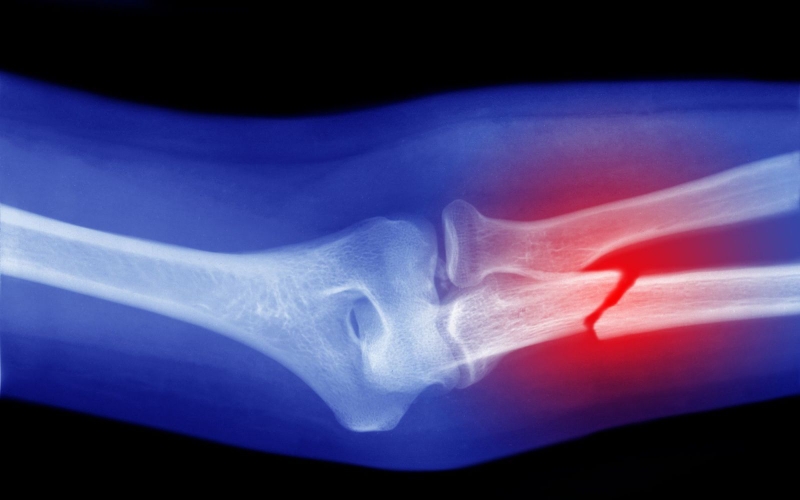

Phương pháp phổ biến nhất là chụp X-quang vùng bị thương để thấy được những biến đổi về xương, tình trạng gãy xương cụ thể, gãy xương cánh tay có nguy hiểm không. Khi thực hiện chụp X-quang, bệnh nhân cần chụp cả 2 bình diện thẳng và nghiêng để đảm bảo không bỏ sót vùng xương nào cần kiểm tra.

Chẩn đoán gãy xương cánh tay qua phương pháp X-quang